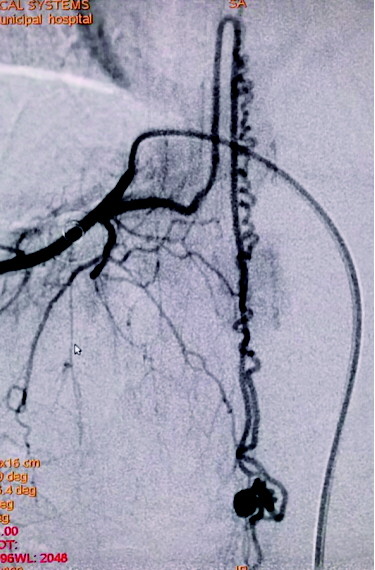

凭借精湛的技术,术中微导管精准地越过脊髓前动脉,为了保证手术的安全性,填入1×2、1×1、和1×1三个超软弹簧圈,造影显示瘘口闭塞,脊髓前动脉能清晰地显影,病变得到治愈。

图A为术前造影的正位图像,主供血为脊髓前动脉,引流静脉的起始部形成一个静脉球,远端呈迂曲状;图B为微导管到位后的超选造影,脊髓前动脉不显影(已越过);图C为栓塞结束后的造影,主供血的血流明显瘀滞,瘘口闭塞,下方的脊髓前动脉仍显影。